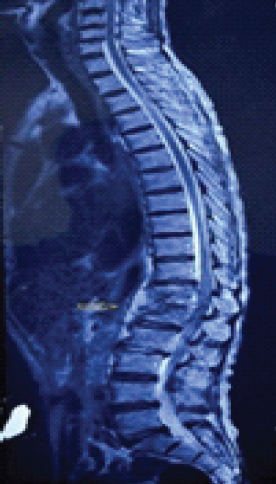

Spinal Aneurysmal Bone Cyst in a Pregnant Patient Presenting with Neurological Symptoms: A Case Report

Bishal Guin , Deepthy Balakrishnan , Arunkumar Sekar , Pavithra Ayyanar

………………………………p.30-33